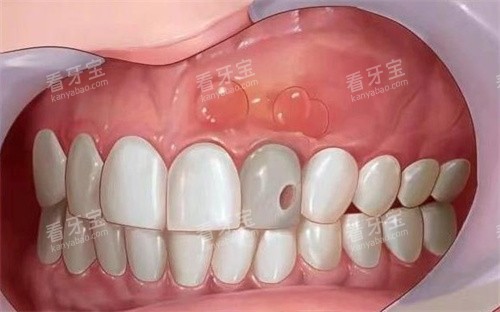

很多人做根管治疗前只看价格,然后要么结果不好反复发炎,要么治疗过程遭罪。其实选机构,这三点比价格更重要。首先是正规性,必须是有资质的口腔机构,小诊所设备消毒不到位,容易引发感染;其次是医生经验,根管治疗是精细活,经验足的医生能比较准找到根管,减少痛苦还能提高治疗好率;然后是服务细节,毕竟看牙本身就紧张,贴心的服务能缓解焦虑,术后也能得到完善的护理指导。